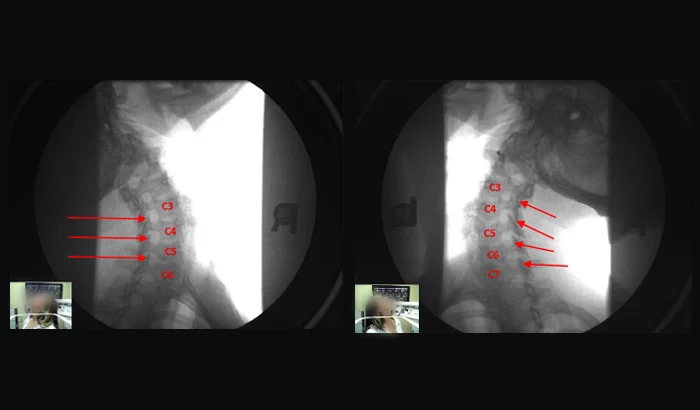

DMX (Digital Motion X-Ray) combines weight-bearing + motion to document cervical ligament damage commonly missed by static X-ray, MRI, and CT.

Digital Motion X-Ray (DMX) evaluates the cervical spine under the conditions that reveal ligament injury: weight-bearing + motion. You can’t test a joint for instability if it doesn’t move. You can’t evaluate a load-bearing structure without load. DMX combines both—so abnormal motion patterns consistent with cervical ligament damage can be seen and documented.

Digital Motion X-Ray (DMX) is a real-time, dynamic imaging system that allows doctors to view the cervical spine while the patient moves. DMX uses fluoroscopy (an “X-ray movie”) to capture cervical motion in real time instead of relying on one still image.

DMX is designed to evaluate cervical ligament function under real-world conditions—weight-bearing + motion—so cervical ligament injury and ligament damage can be identified and documented when static or unloaded imaging fails to reveal the true injury mechanism.

DMX is one of the few tests that evaluates cervical stability under weight-bearing + motion, helping document subtle ligament injury/laxity (“sub-failure” injury) that may not be visible on routine MRI, CT, or static X-rays.

DMX is typically performed with the patient standing (loaded) while the neck is guided through controlled motion. The study captures the vertebrae moving during motion, rather than a single static image.